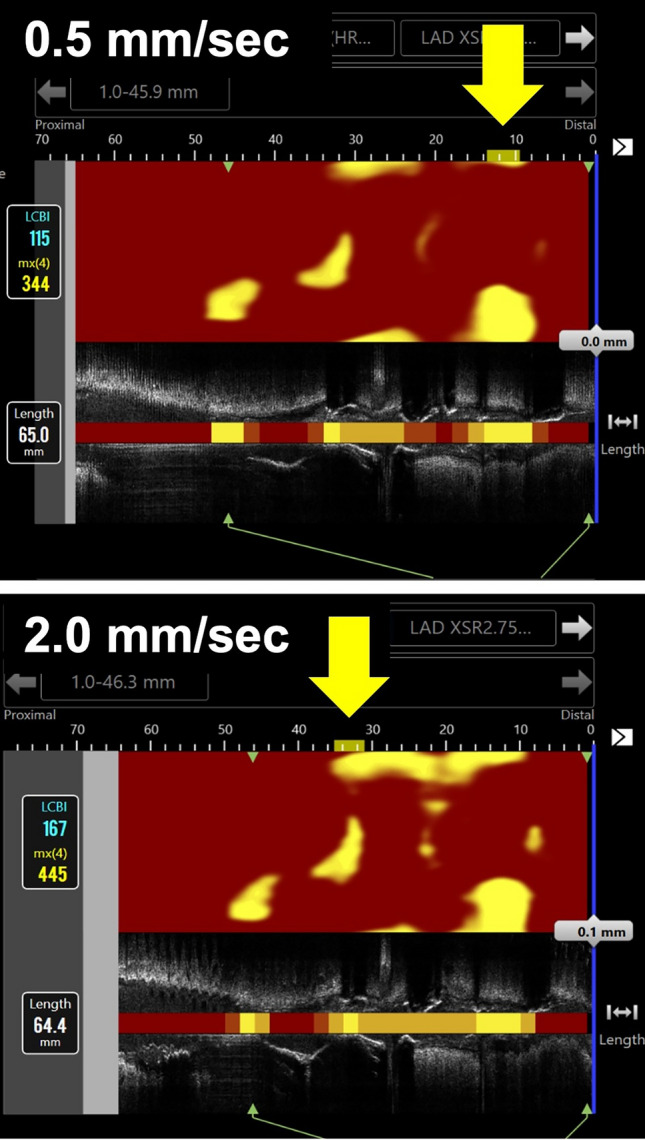

Near-infrared spectroscopy-intravascular ultrasound (NIRS-IVUS) can assess the amount of lipid core plaque, and the latest generation catheter allows for imaging at several different pullback speeds. The purpose of this study was to investigate the impact of pullback speed on evaluation of lipid core plaque using the latest generation NIRS-IVUS catheter. Patients with coronary artery disease who underwent coronary angiography or percutaneous coronary intervention with NIRS-IVUS examination at 2 different pullback speeds (0.5 and 2.0 mm/sec) for the same vessel were enrolled. The values of lipid core burden index (LCBI) and maxLCBI4mm were compared between the images recorded with pullback speeds of 0.5 and 2.0 mm/sec, and match or mismatch of the location where maxLCBI4mm was detected was investigated. In a total of 286 NIRS-IVUS image sets, the location of maxLCBI4mm measured at 0.5 and 2.0 mm/sec was mismatched in 81 (28.3%) image sets. In comparison by vessel type, 20.8% were mismatched in LAD, 31.1% in LCx, and 37.8% in RCA (p = 0.023). In 205 image sets with matched maxLCBI4mm location, the maxLCBI4mm value at 2.0 mm/sec was significantly greater compared with that at 0.5 mm/sec (348.0 vs. 302.0 in median, p < 0.001). In a substantial proportion of patients, the location of maxLCBI4mm values measured at 0.5 and 2.0 mm/sec was mismatched. In the image sets with matched maxLCBI4mm location, the maxLCBI4mm value at 2.0 mm/sec was significantly greater compared with that at 0.5 mm/sec. These results should be noted when applying the cut-off values of maxLCBI4mm recorded at 2.0 mm/sec.